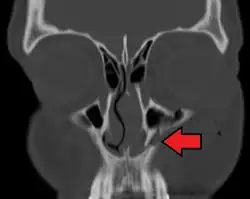

- The body of the maxilla: pyramid-shaped; has an orbital, a nasal, an infratemporal, and a facial surface; contains the maxillary sinus.

- the maxillary sinus

The maxillary sinus appears as a shallow groove on the nasal surface of the bone about the fourth month of development, but does not reach its full size until after the second dentition.

The maxillary sinus presents the appearance of a furrow on the lateral wall of the nose. In the adult the vertical diameter is the greatest, owing to the development of the alveolar process and the increase in size of the sinus.

A maxilla fracture is a form of facial fracture. A maxilla fracture is often the result of facial trauma such as violence, falls or automobile accidents. Maxilla fractures are classified according to the Le Fort classification.